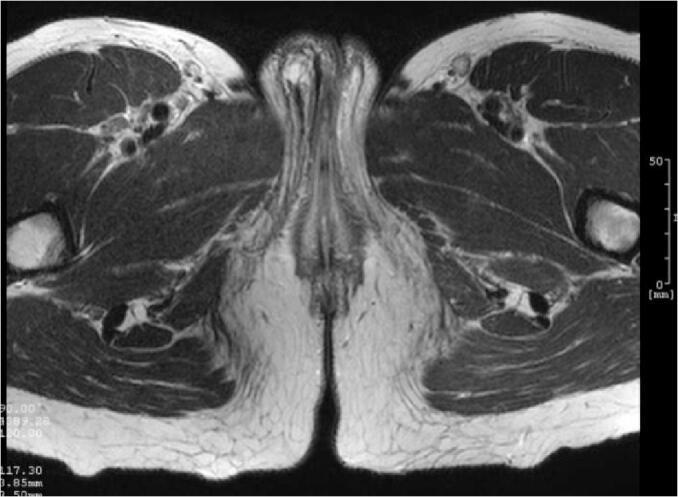

A 37-year-old woman presented with a right labium majus thickening with no palpable mass, which had been evolving for a few months. A partial right labium majus ablation was performed at the request of the patient for esthetic reasons. The lesion was most histologically similar to CALME (childhood asymmetric labium majus enlargement). The lesion was benign, but several other differential diagnoses were considered. Two years after the surgery, there had been no recurrence. To our best knowledge, this is the first such case reported in an adult.

一名37岁女性因右侧大阴唇增厚就诊,未触及肿块,这种情况已持续数月。应患者出于美观考虑的要求,进行了右侧大阴唇部分切除术。组织学上,该病变与儿童期不对称性大阴唇增大(CALME)最为相似。病变为良性,但也考虑了其他几种鉴别诊断。手术后两年,未出现复发。据我们所知,这是首例在成人中报道的此类病例。